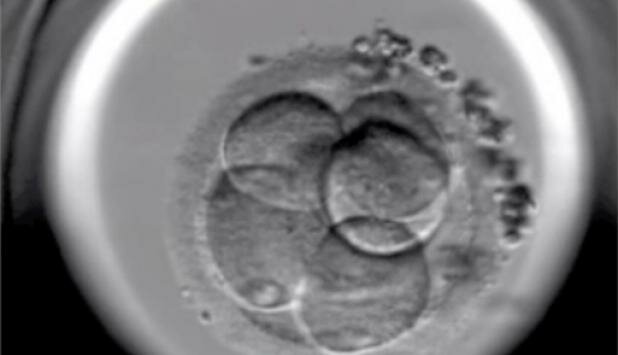

• Los nacimientos in vitro

Los nacimientos in vitro

Nació el primer bebé "a la carta" libre de la Anemia de Fanconi que padecía su hermana y cuyas células de cordón sirvieron para curarla. La técnica de análisis embrionario (diagnóstico preimplantación tras fecundación in vitro) nos permite evitar el nacimiento de niños con determinadas enfermedades hereditarias.